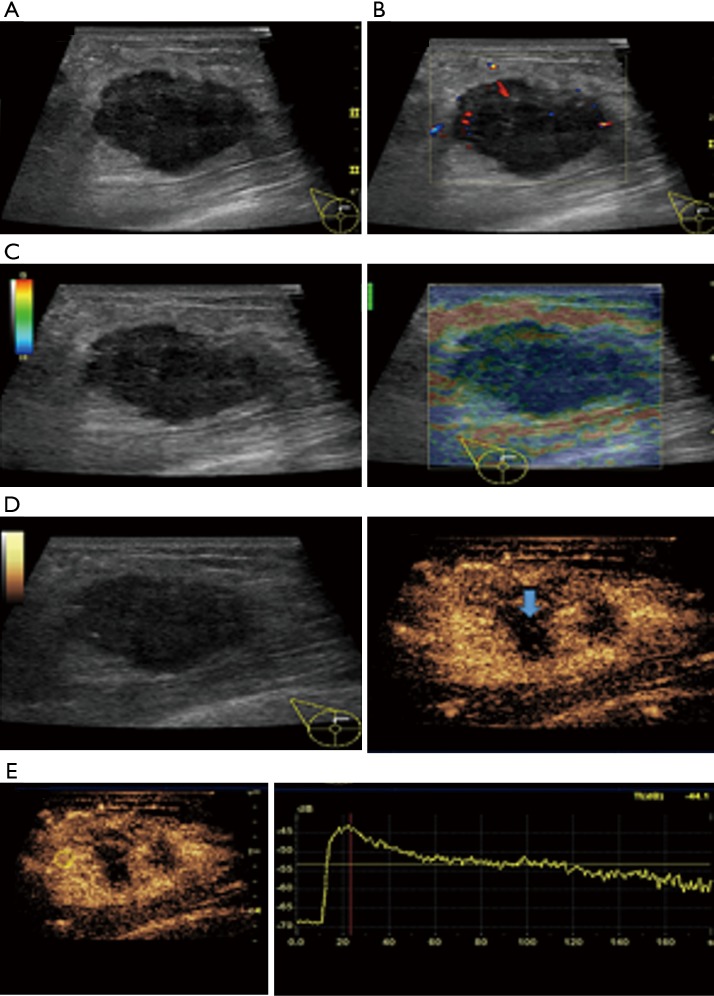

In this study, CEUS of LABC showed high enhancement, and its internal and peripheral blood vessels showed “solar sign” (Figure 1). Relevant studies showed (25) that angiogenic factors could stimulate the breast tissue to produce new blood vessels that extend into the tumor in malignant tumors. And then it would form a network of blood vessels that changed with the growth and necrosis of the tumor. Due to the anisotropy of malignant tumor growth, its internal vascular path was messy, twisted and variable. The characteristic of “solar sign” was often seen as an important indicator for the diagnosis of benign and malignant tumors (23,25). In this study, the tumors of invasive ductal carcinoma all presented as “fast in and slow out”. Analysis suggested that there might be abundant arterial regeneration in the tumor. They were rapidly enhanced. Related studies showed that malignant tumors were composed of abnormal blood vessels with increased tortuosity. It tended to increase flow resistance. At the same time, hypoxia and acidosis decreased red blood cell fluidity. They could also lead to venous insufficiency, poor reflux, and thrombosis, which leaded to form a slow withdrawal (27-29). Some study revealed that breast cancer presented as “fast in and fast out”. It might be because of the formation of arteriovenous fistula inside the tumor. However, Wan et al. [2012] (25) showed that the enhancement mode could also be “fast in and slow out” in benign tumors. It might be related to the blood supply characteristics of the breast tumor. So the mode of enhancement cannot be used as a distinguishing feature of benign and malignant breast tumors. In addition, in this study, 11 lesions (11/40, 27.5%) had no, equal or low enhancement areas, including 5 lesions (5/40, 12.5%) had no continuous enhancement areas. In 3 of the 5 lesions, the internal cystic area was found in conventional ultrasound, but the area of no enhancement in CEUS was significantly larger than that in conventional ultrasound. In 2 lesions, no cystic area was found in conventional ultrasound, but CEUS showed non-liquefaction necrosis area without enhancement (Figure 2). In addition, for non-mass breast cancer, it was difficult to be presented in conventional ultrasound. CEUS could show relatively clear boundaries. In particular, CEUS could clearly show the area of lesions and internal vascular conditions, assisting in diagnosis and guiding the area of puncture biopsy (Figures 3,4). Therefore, CEUS was more likely to detect muscle or skin infiltration than conventional ultrasound, providing a reference for accurate clinical T staging of LABC.

Figure 2.

The features of conventional ultrasound, SE and CEUS (mass type) of locally advanced invasive ductal carcinoma in 1 case. Female, 39 years old, the right breast was touched the mass. (A) Conventional ultrasound showed irregular hypoechoic mass in the upper quadrant of the right breast with heterogeneous internal echo, and the aspect ratio was less than 1; (B) multiple short striped blood flow signals can be seen in CDFI, and the blood flow grade was II; (C) SE score was 4, which was relatively hard; (D) under the CEUS mode, the tumor presented heterogeneous and high enhancement with main blood vessels both extending into the tumor and around the periphery. The enhancement area was larger than that of conventional ultrasound. The arrow indicated area was no enhancement; (E) the TIC curve of CEUS showed that enhancement mode of lesion was “fast in and slow out”. CEUS, contrast-enhanced ultrasonography; CDFI, color Doppler flow imaging; SE, strain elastography; TIC, time-intensity curve.